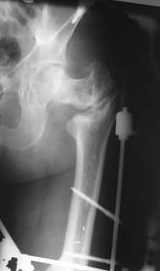

Уважаемые коллеги! Нужен совет.Больной Х., 21 год, ДЗ: ложный сустав вертельной области правого бедра.

Травма 8 мес. назад, ДТП, получил закрытый межвертельный перелом правого бедра. Лечился в городской больнице одного из городов-спутников г. Караганды скелетным вытяжением в течение 3 недель, затем кокситной гипсовой повязкой 2 мес. В настоящее время имеется укорочение конечности на 7 см, умеренная боль в вертельной области; ходит без костылей, полностью нагружая больную конечность, при нагрузке отмечается смещение дистального отломка проксимально примерно на 1,0 см.; объем движений в коленном суставе сохранен; при пальпации отломков боли нет, умеренная патологическая подвижность. Планируем внеочаговый остеосинтез спице-стержневым аппаратом, дистракция до восстановления длины бедра, вторым этапом остеосинтез стержнем Гамма. Есть надежда, что на дистракции пойдет сращение и у больного хватит терпения завершить лечение в аппарате.

По опыту подобных случаев, аппарат лучше на бедро, без таза пока. В проксимальный фрагмент 3 стержня по оси шейки. Дистальный - хватит 1 стержня или 2 спиц в дистальном метафизе и 1 стержня вверху. Если планируете гвоздь, надо с гиперкоррекцией восстановить длину и ось, т.е. вальгизировать проксимальный отдел. При наложении аппарата сделать остеоклазию, добиться уверенной подвижности. Регенерат не нужен, тяните на пределе переносимости пациентом - хоть 2 см/сут. Обычно меньше.

В приложении пример пациента, близкого по картине к тому, что представил Виктор (варус и смещение периферического отломка на поперечник кзади). Сделали как раз то, что Виктор исходно намеревался - аппаратная коррекция и затем гамма.